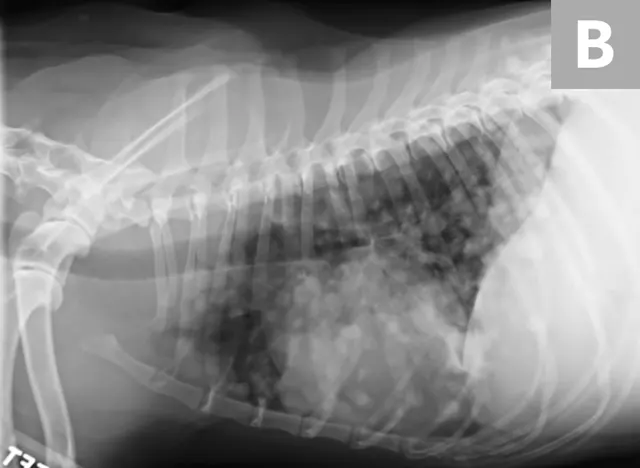

Abdominal and thoracic radiography (mass effect or pulmonary metastases; Figure 5)

Additional radiography studies of affected anatomic sites (Figure 7)